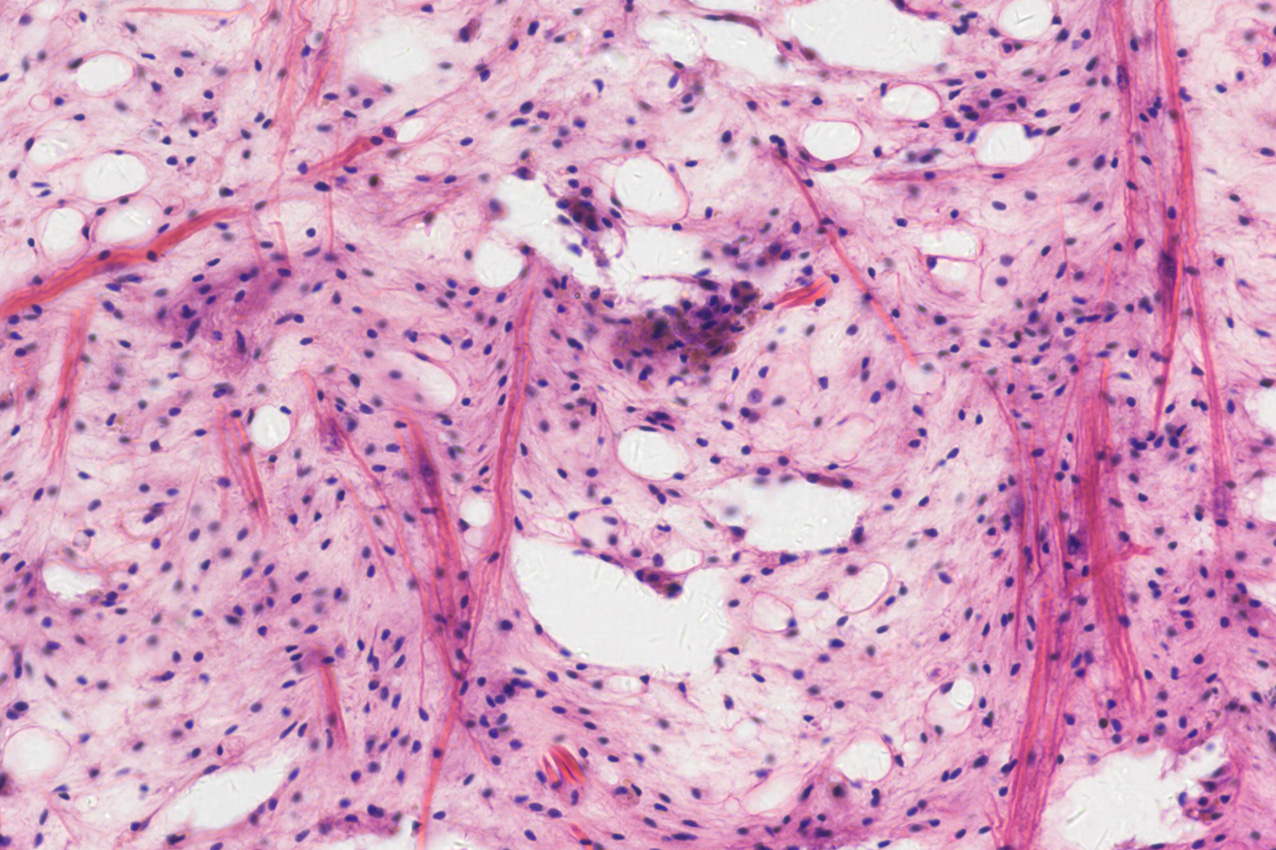

Whole-slide imaging (WSI) digitizes biological tissue sections at high resolution, enabling precise analysis of tissue structures and cellular morphology. Modern high-throughput scanning can cover entire slide areas in a single experiment, capturing multiscale information from nuclei to tissue-level structures. WSI plays a pivotal role in pathology diagnostics, drug development, and large-scale histological studies.

Because tissue sections are large, structurally complex, and often involve multiple staining or fluorescence labels, high-throughput scanning systems impose demanding requirements on imaging devices: Large FOV format, high resolution, high-speed acquisition, and accurate color reproduction. Furthermore, quantitative precision must be ensured to meet the rigorous standards of professional pathology analysis.